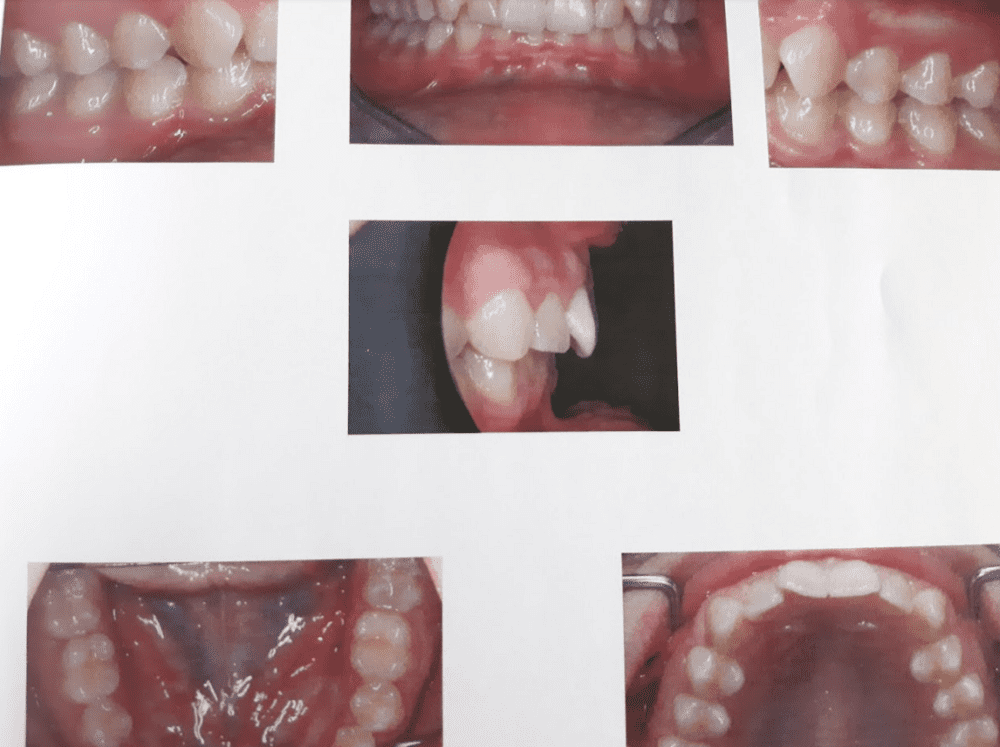

So i went to my Ortho today, and he gave me a twinblock. I asked him if it'll fuck with my maxilla and he kept kind of refusing to answer it properly he just said "it will change your side profile a tiny bit...." so me and my mom both agreed on looking into a surgical option. However could i get it with this kind of bite? And from what i read you will have to get braces and a wisdom tooth extraction before it, will that hurt my jaw?

My bite and Xray (dont mind the earbud)

My bite and Xray (dont mind the earbud)